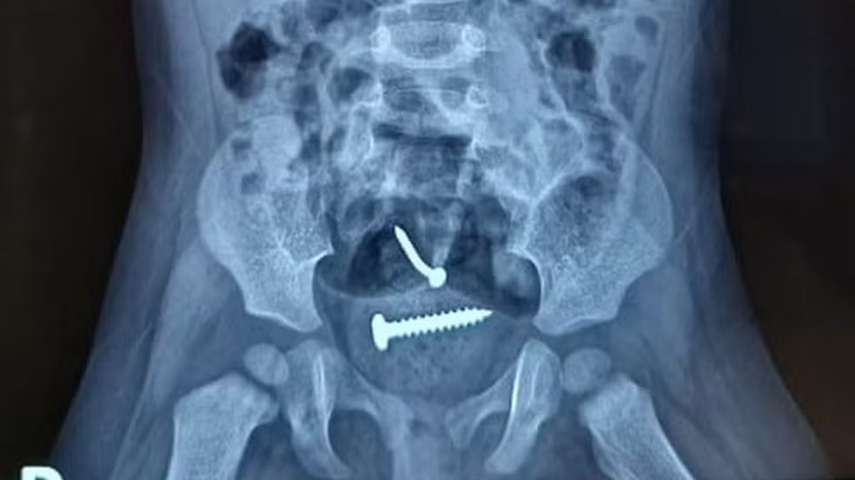

Laudo médico diz que bebê que engoliu parafuso não foi violentada; pai foi solto

Laudo médico diz que bebê que engoliu parafuso não foi violentada; pai foi solto | Foto: Reprodução

O laudo médico da bebê de 1 ano, que estava com um prego e parafuso dentro do corpo, revela que não houve violência sexual. O suspeito de ter agredido mãe e filha prestou depoimento na delegacia da cidade de Pedro II e negou ter abusado da bebê.

A sua companheira também negou, que o pai tenha cometido algo contra a criança. O laudo também mostrou que a criança engoliu os objetos e que os mesmos foram expelidos de forma natural, não precisando de intervenção cirúrgica.